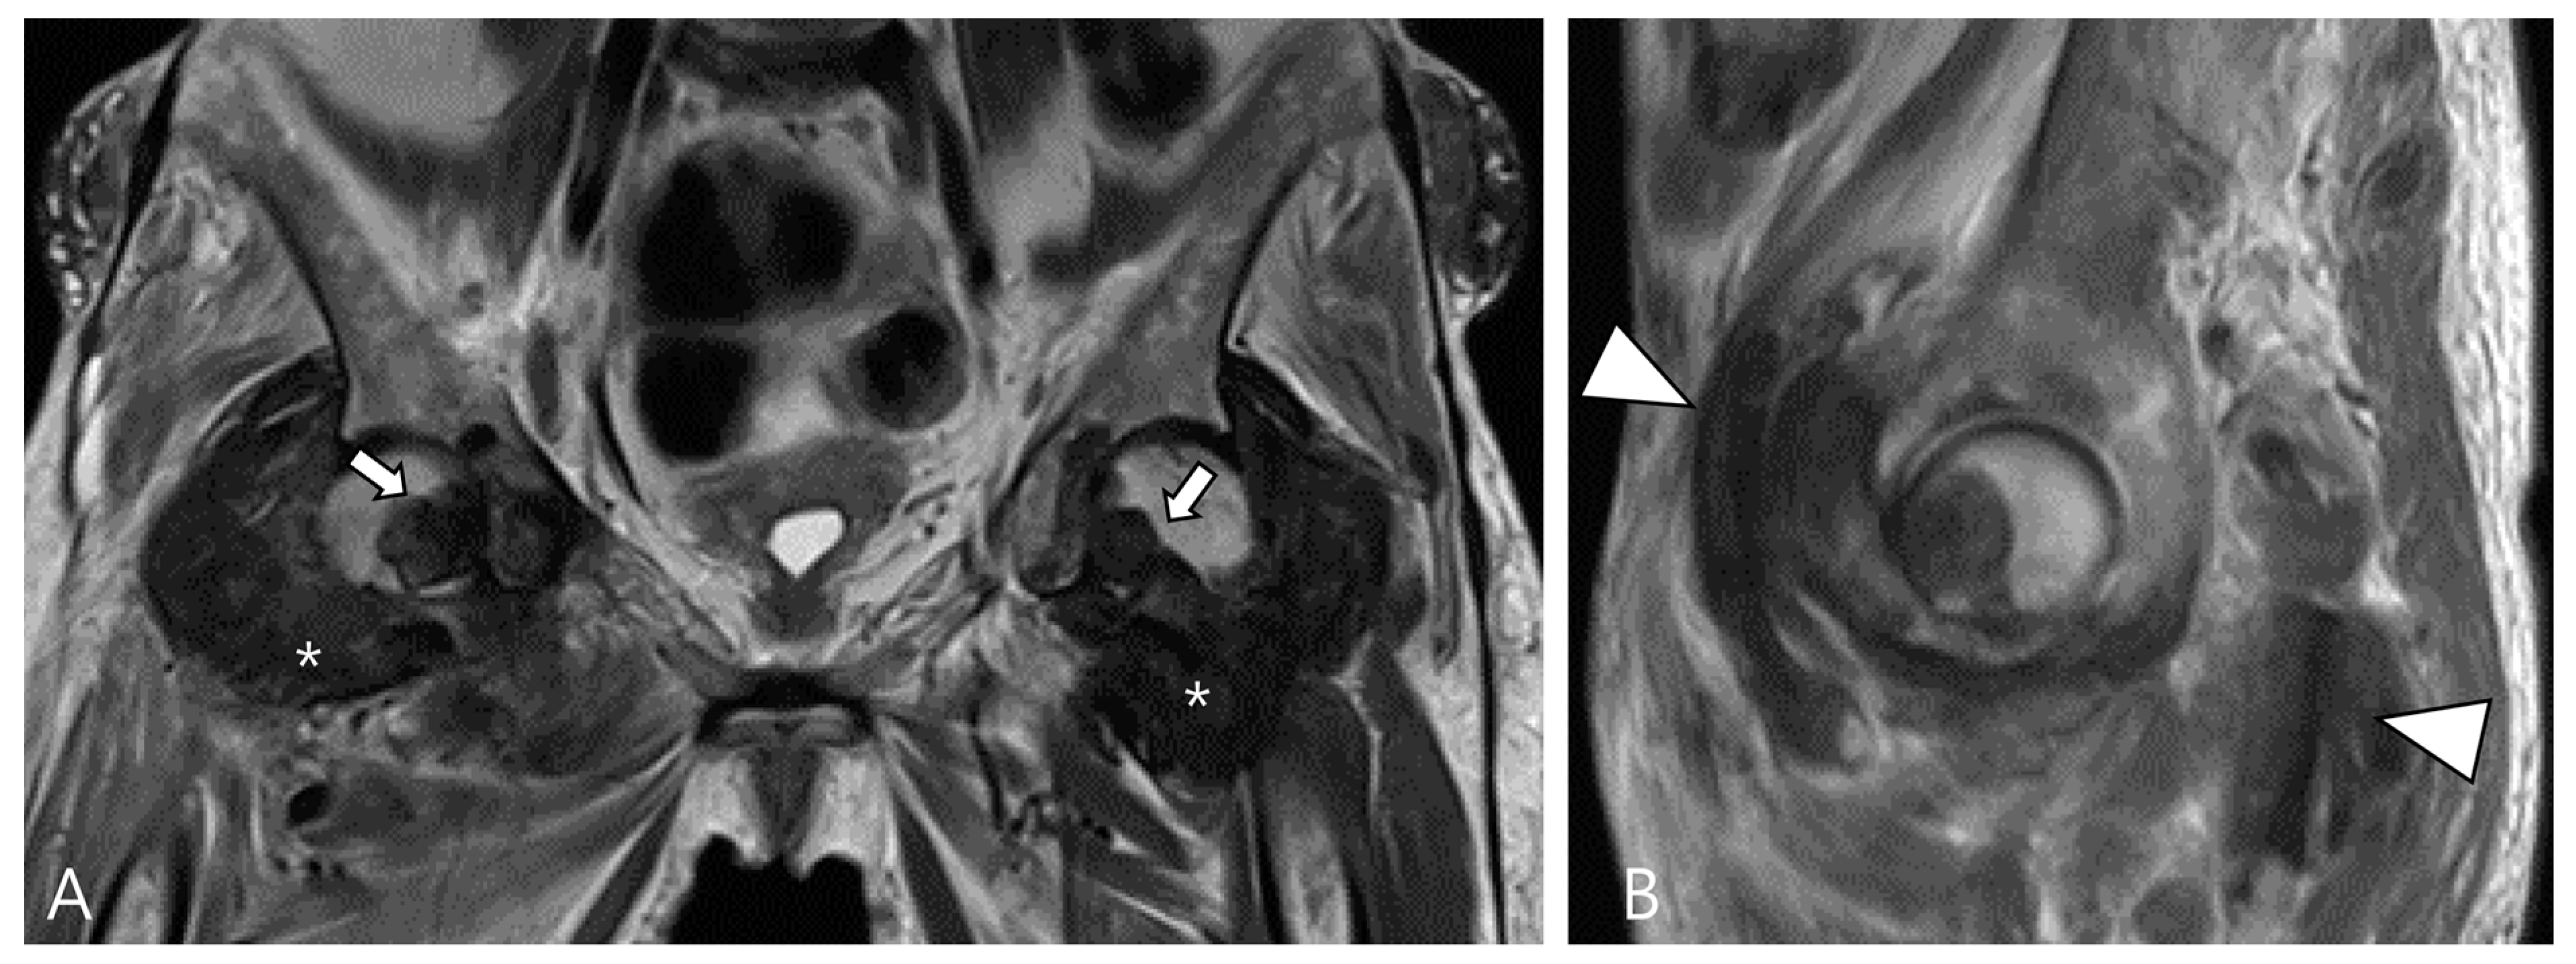

Amyloid arthropathy is a complication associated with long-term hemodialysis [49]. It arises from the deposition of a distinctive form of amyloid, derived from circulating β2-microglobulin, within the synovial fluid, bone, and periarticular tissues. Increased serum levels of β2-microglobulin in hemodialysis patients result from the ineffectiveness of both hemodialysis and peritoneal dialysis membranes in filtering this substance [49,50]. Commonly affected joints include the shoulder, hip, femur, and knee [55]. On MRI, amyloid deposition exhibits a heterogeneously low SI on both T1WI and T2WI, which can resemble intra-articular D-TSGCT [50]. Despite the short T2 relaxation time characteristic of amyloid-containing tissue due to their hypocellular and fibrous nature, amyloid deposition does not demonstrate a paramagnetic effect on GRE sequences [49]. While D-TSGCT typically manifests as monoarticular arthropathy, amyloid arthropathy presents as symmetric polyarthritis with joint or periarticular swelling, accompanied by tendinous amyloid deposition in periarticular areas (Figure 12) [49]. Notably, a clinical history spanning more than 5 years since the initiation of hemodialysis can be a crucial diagnostic clue [55].

Figure 12.

A 62-year-old female with amyloid arthropathy in both hip joints. (A) Coronal T2WI shows periarticular soft tissue masses (asterisks) extending to intra-articular space with heterogeneously low SI in both hip joints. Bony erosions at both femoral heads (arrows) are combined. (B) Sagittal T2WI shows that the mass infiltrates into the adjacent tendon and muscles (arrowheads).